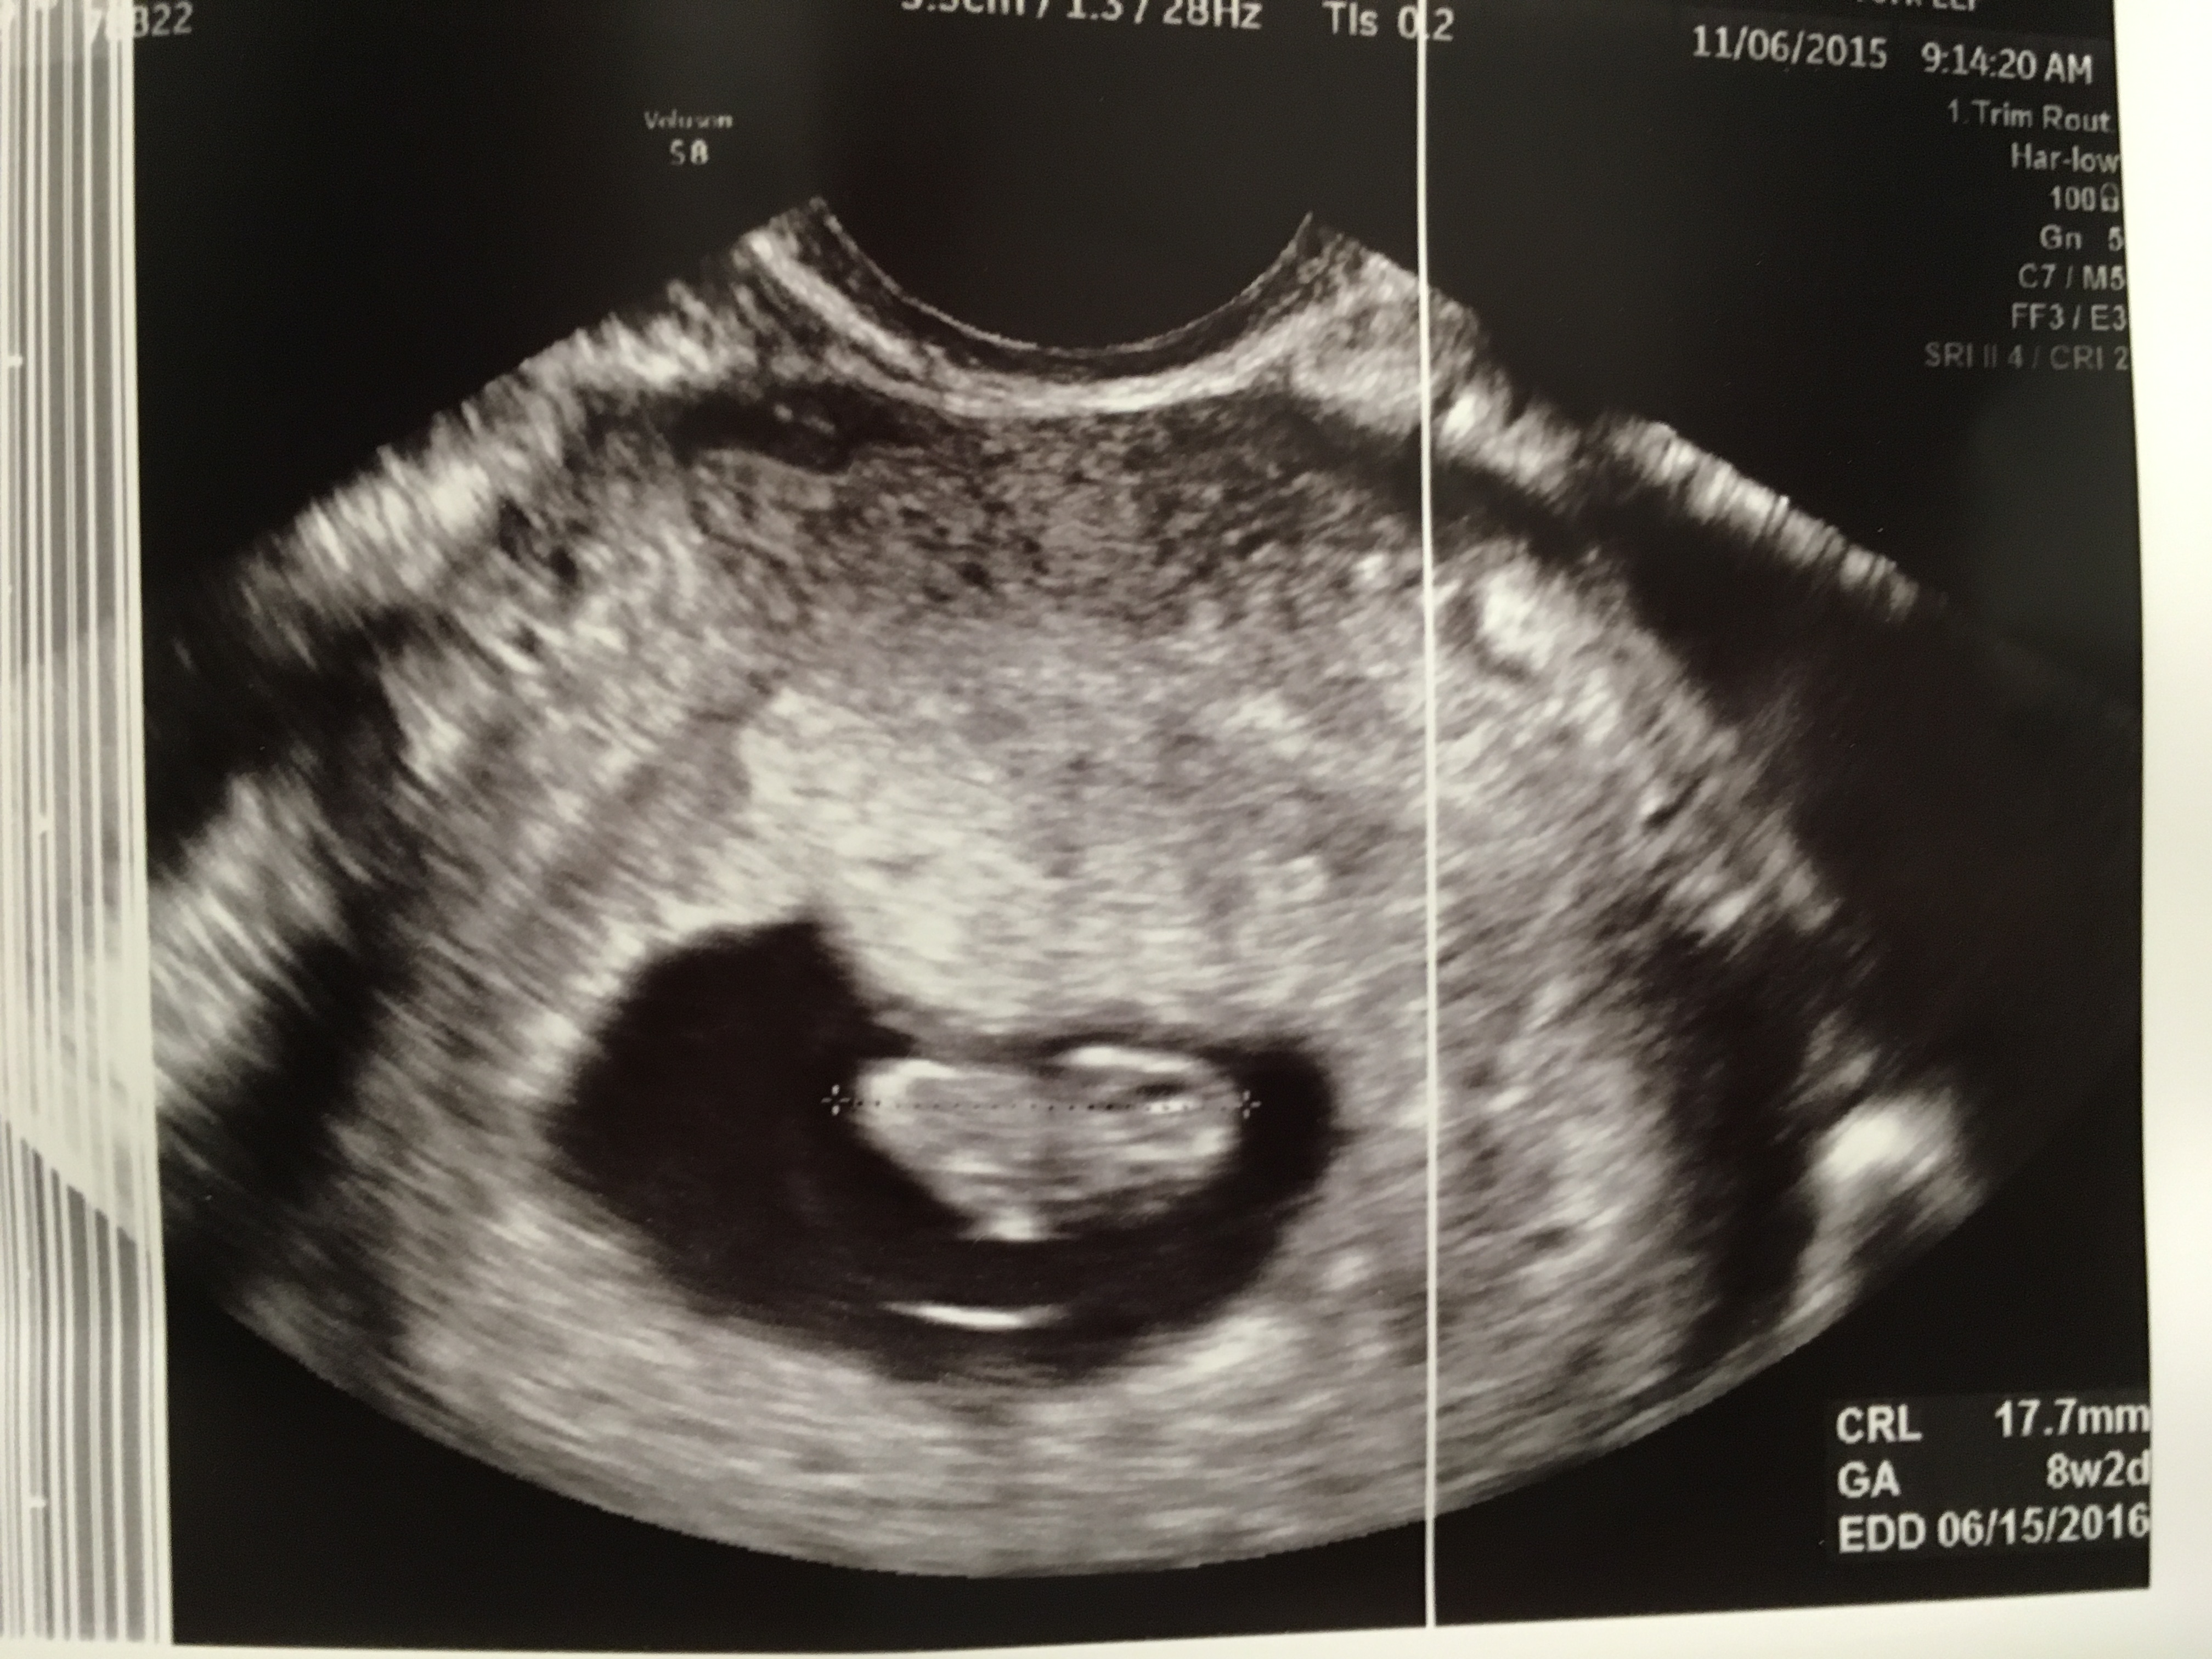

@binnie505- EDD 6/12/16 Welcome and Congrats!

9/15/2015: BFP HCG - 400, 9/17/2015: HCG - 827, 9/21/2015 - HCG 3,327!Had my us today at 8+0 and they've taken away my training wheels. No more estrace or PIO after next Wednesday and I've been turfed to the regular OB!